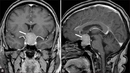

Ameliyat Sonrası BakımHipofiz ameliyatı sonrasında dikkat edilmesi gereken bazı noktalar vardır:

SonuçHipofiz ameliyatı, hipofiz bezindeki hastalıkların tedavisinde önemli bir yöntemdir. Cerrahi işlem, uzman bir ekip tarafından titizlikle gerçekleştirilmelidir. Ameliyat öncesi ve sonrası süreçler, hastaların tedavi sürecinin başarısı için kritik öneme sahiptir. Hastalar, sağlık durumlarını ve tedavi seçeneklerini doktorları ile detaylı bir şekilde görüşmelidir. Ek BilgilerHipofiz ameliyatı, hastaların yaşam kalitesini artırmak için önemli bir tedavi seçeneğidir. Ancak her cerrahi işlemde olduğu gibi, riskleri ve olası komplikasyonları da göz önünde bulundurmak gerekir. |